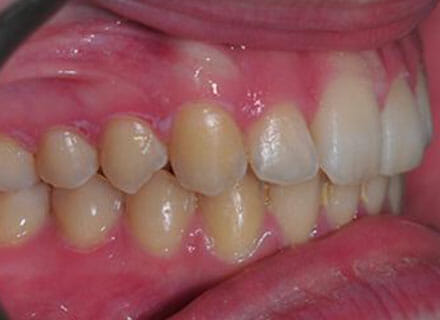

In this case, the upper incisors had a pushed back appearance and they were twisted. the smile was narrow – when the patient smiled the sides of the smile were in shadow. we used clear brackets to gently untwist and straighten the front teeth while widening the upper arch/jaw to broaden the smile. this patient was beaming for the first time in just 12 months.